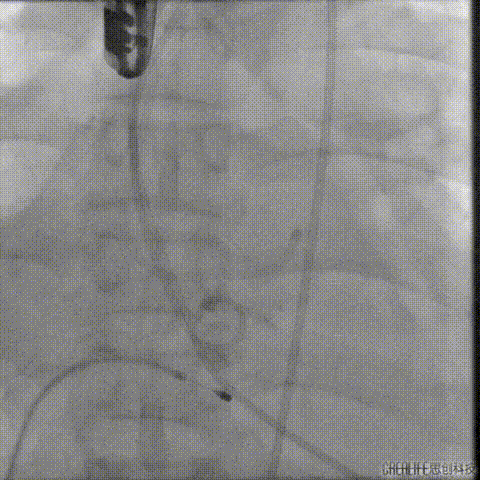

经瓣架网眼挂上指引管

反复确认指引管经瓣架网眼

指引管经瓣架网眼

经网眼置入导丝

置入4.0mm*23mm微创冠脉支架

定位并释放支架

退出球囊扩张突入瓣架部位

复查冠脉造影

多体位复查冠脉造影